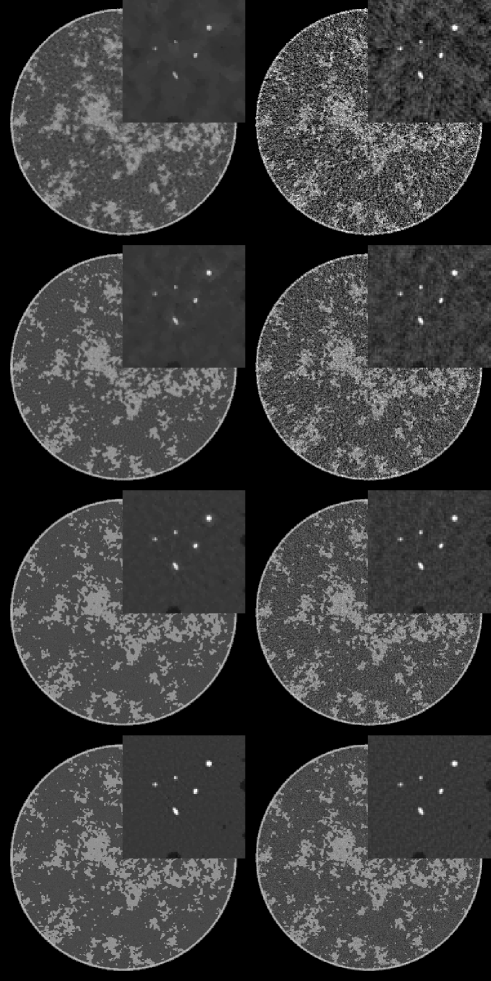

IV-A image reconstruction from noiseless data

In Fig. 2, we show images reconstructed from 64 to 512 projections for both TV-minimization and filtered back-projection (FBP). For TV-minimization in this study we set , which corresponds to a very tight data constraint. As noted above the sparsity of the gradient magnitude is on the order of 50,000. Accordingly, from CS-based arguments, one could only expect to start to achieve accurate reconstruction when the number of measured line integrals exceeds 100,000, which in this case means 100 projections. An important part of CS theory deals with computing the factor between the sparsity level and necessary number of measurements for accurate recovery. This factor is unknown for TV-minimization applied to the X-ray transform, but we can see from the reconstructions that the accuracy is greatly improved in going from 128 views to 256 views. There is still a perceptible improvement in the image recovery in going to 512 views, which still represents an under-determined system despite the fact that 512 views is normally not thought of as a sparse-view data set. Again, it is the complexity of the phantom which is responsible for this behavior. The accompanying FBP results give an indication on the ill-posedness of reconstruction from the various configurations with different numbers of projections.

The results for the micro-calcification ROI are interesting in that this particular feature of the image is recovered for all data sets down to the 64-projection data set. This is not too surprising because the micro-calcifications are certainly sparse in the gradient magnitude. But this result emphasizes that the success of an image reconstruction algorithm depends also on the imaging task and the subject.

For the larger goal of determining the optimal number of views, it is clear that ”structure noise” – artifacts due to the complex object function– can play a significant role for this breast phantom.